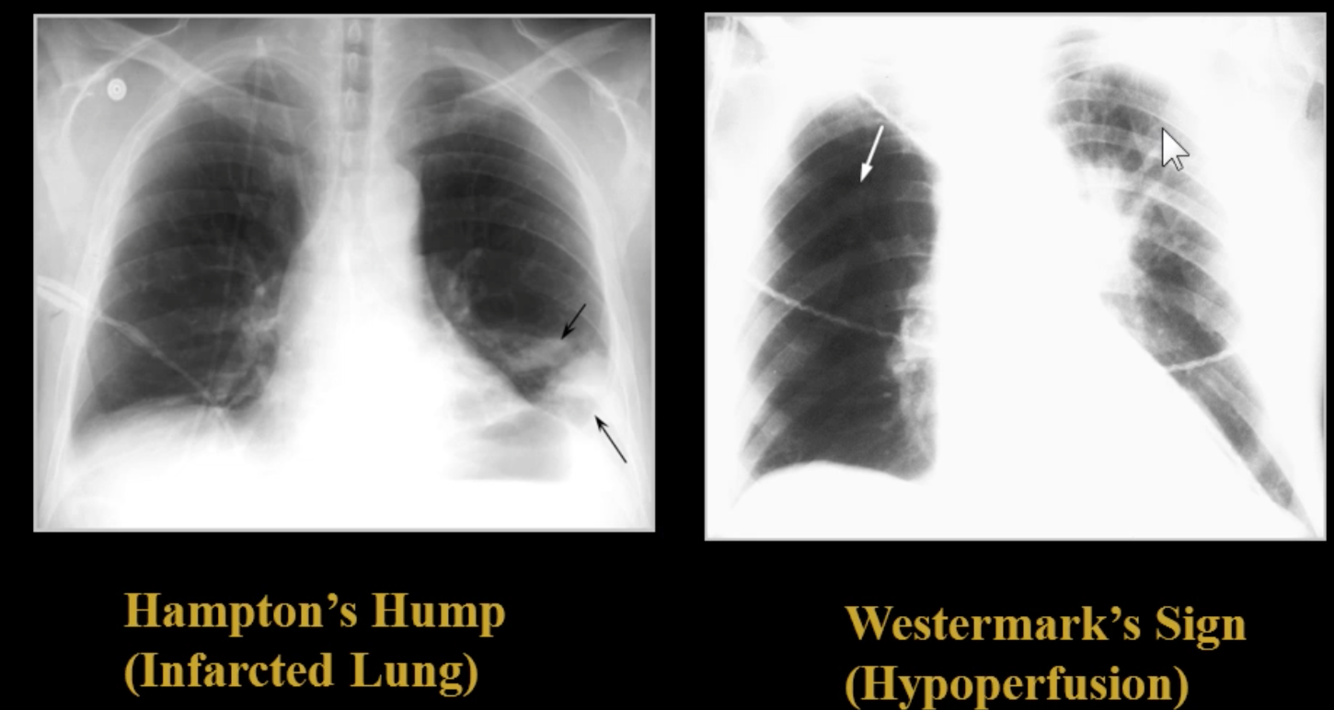

What is CXR like on patients with PE?

CXR is typically normal but it is used to exclude other processes.

A couple findings that can sometimes be found are Hamptom’s Hump (showing infarcted area of lung) or Westermark’s sign (showing hypoperfusion of a lung–the lung is more translucent than usual)